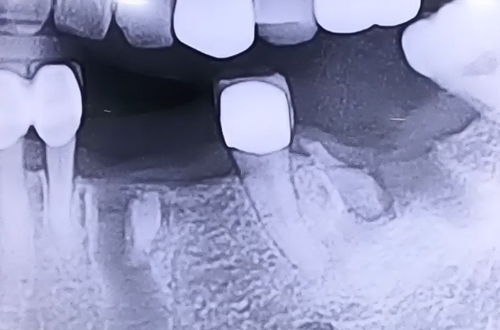

타 병원에서 왼쪽 아래 치아들을 발치하진 후 며칠이 지나도 아물지 않고 통증이 계속되어 내원해 주셨던 환자분이십니다.

발치한 부분을 자세히 확인해보니 발치할 때 치아 뿌리가 파절되어 잇몸 내부에 뿌리들이 남아있는 상태인 것이 발견되었는데요.

이 뿌리들을 깨끗하게 빼고 주변 염증까지 제거해 드린 뒤, 두달 정도 충분히 아물 수 있도록 기간을 두고서 뼈이식임플란트를 진행하였습니다.